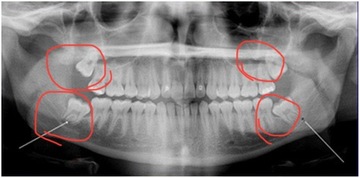

親知らず、どうしたらいいの?

親知らずが気になる…という方、意外と多いのではないでしょうか?

「奥の歯ぐきが腫れて痛い」「物が詰まりやすい」「歯ブラシが届きにくい」

そう感じたことがあるなら、親知らずが関係しているかもしれません。

親知らずは、まっすぐ生えていなかったり、半分だけ歯ぐきから出ていたりすることが多く、プラーク(歯垢)が溜まりやすい場所です。

その結果、歯ぐきが腫れたり、膿が出たり、口が開きにくくなったりといった症状が出ることがあります。

では、抜いたほうがいいの?

答えは「ケースバイケース」。

トラブルを繰り返していたり、

他の歯に悪影響を与えている場合や、

親知らずにむし歯ができているなどの場合は、

抜歯を勧められることが多いです。

でも、まっすぐ生えていて、きちんと磨けているなら、必ずしも抜く必要はありません。

親知らずに痛みが出る症状

・腫れ

・痛み

・口が開けづらい

・頭痛、肩こり

などがあります。これらの症状が頻繁に起こる方がいれば抜歯をおすすめします。

これも気になりますよね。

親知らずの位置や生え方によって、抜歯の難しさや痛みの感じ方は変わります。

下の親知らずや横向きに生えている場合は、歯ぐきを開いたり、歯を分割して抜くこともありますが、処置中は麻酔が効いているので痛みはほぼありません。

抜歯後は多少の腫れや痛みが出ることもありますが、数日で落ち着くことが多いです。

気になるなら、まずは歯科で相談を!

レントゲンで生え方や周囲の状態を確認してもらうことで、適切な判断ができます。

気づかぬうちに、親知らずがトラブルの原因になっていることも。

お口の健康を守るためにも、早めにチェックしておきましょう!